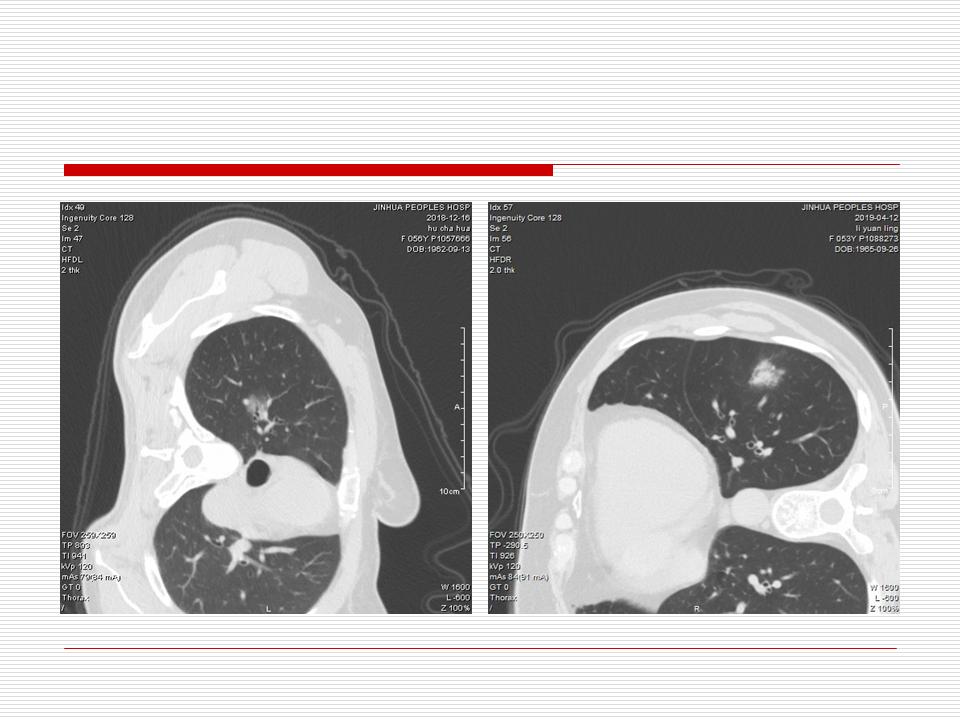

肺部阴影永恒且最重需要鉴别的是:到底是炎症还是肿瘤?但临床的病例中的影像表现难以界定或有些肿瘤特征,同时又有些炎症特点是非常常见的情况。作为临床医生我们怎么去总结分析,并找到之所以是炎症或之所以是肿瘤的细微差别或特点非常重要,也非常有用。2019.12.7浙江省2019年胸心外科学学术年会在宁波召开时,我的临床病例分析与经验总结<那些像肺癌的炎症与像炎症的肺癌>获得在大会交流的机会,以下为该PPT的内容,与你分享,希望对同道有益,有借鉴与启迪。若有探讨与进一不完善的建议,欢迎文末留言讨论: